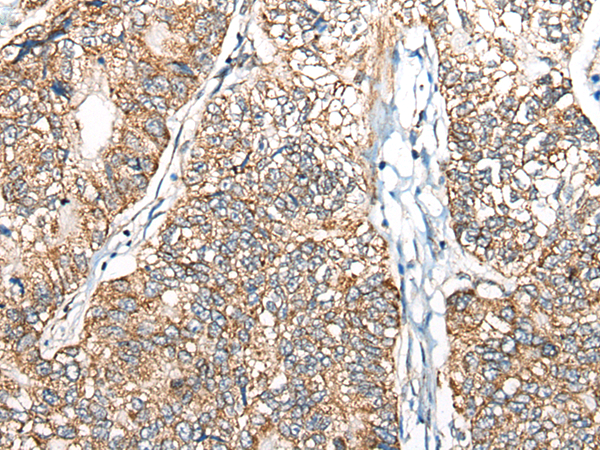

Name of antibody: |

NADK2 |

Applications: |

ELISA, WB |